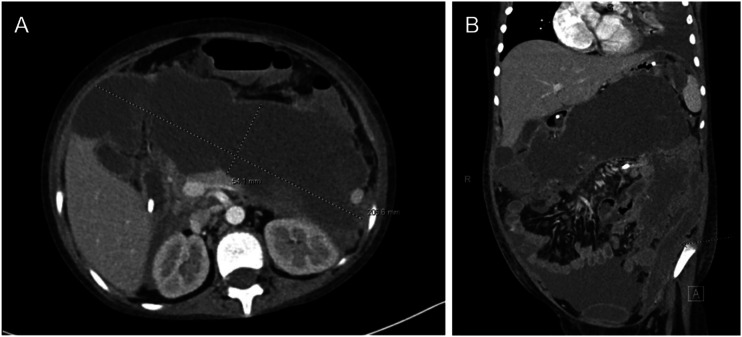

Abstract Image